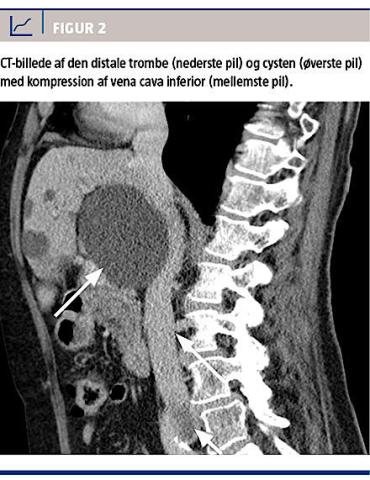

Der blev foretaget CT af thorax og abdomen med henblik på LE samt bekræftelse af cystens størrelse

og placering (Figur 2). Ved CT’en afkræftedes LE, men der blev konstateret en stor levercyste på 6 ×

10 × 7 cm, der komprimerede VCI med dillatation under cysten (Figur 2), samt at trombedannelsen strakte sig helt op i den distale VCI.